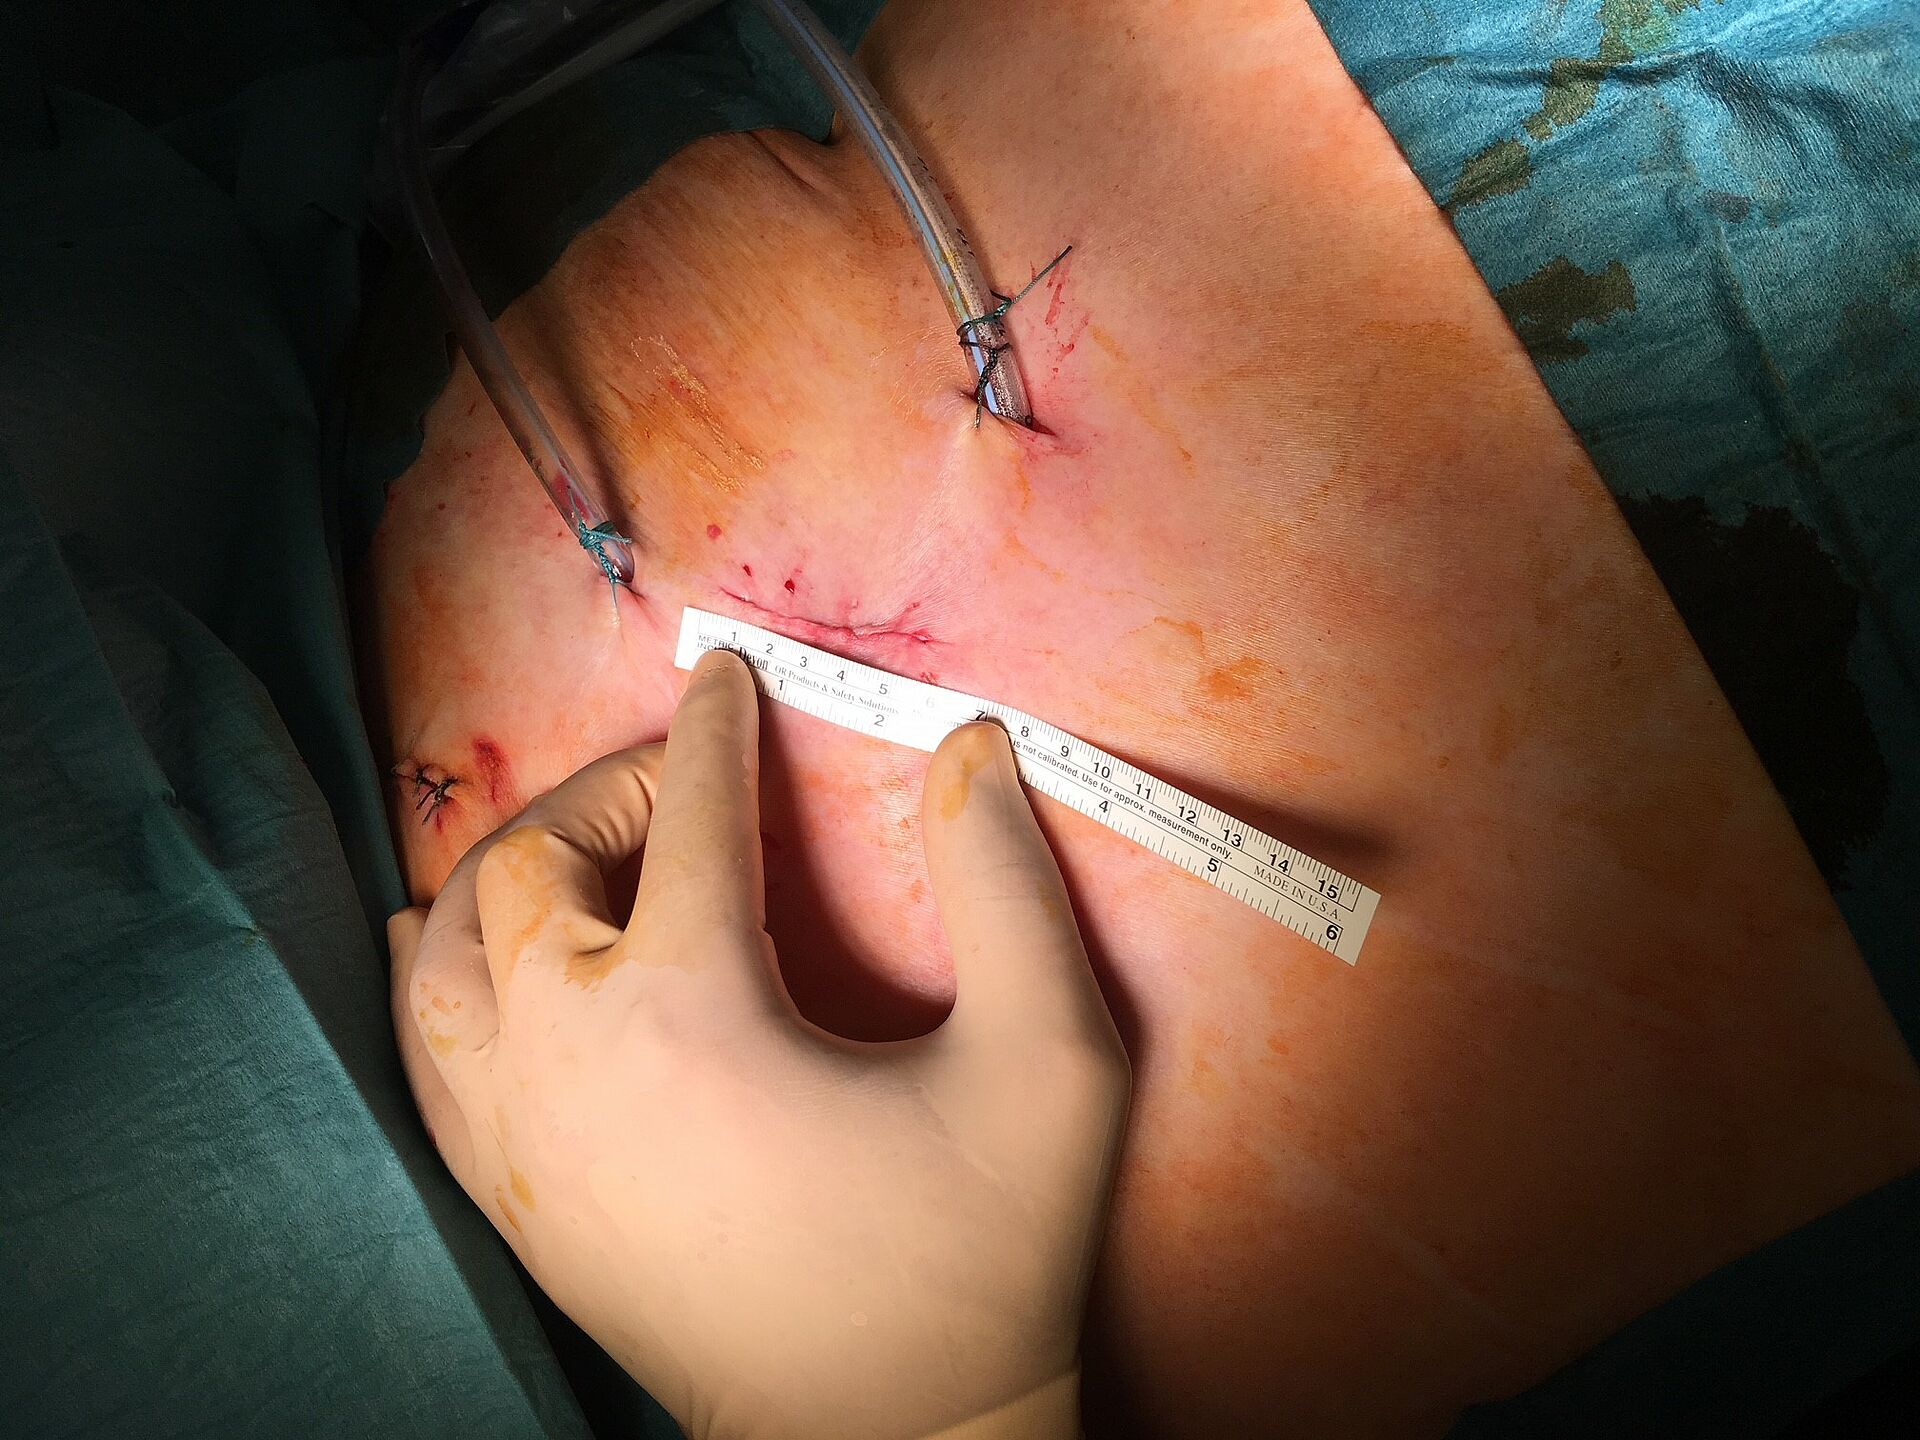

Mit dem Begriff "minimal-invasive Thoraxchirurgie" werden Schlüsselloch-Techniken für Operationen bezeichnet, in der Thoraxchirurgie eine noch junge Methode, die sich rasant entwickelt. In unserer Klinik kann diese schonende Technik sogar bei der Therapie von Lungenkrebs zum Einsatz kommen.

VATS-Lobektomie

Technisch hoch anspruchsvolle Lungenoperationen können in unserer Klinik auf endoskopische Weise videoassistiert vorgenommen werden (VATS: Video-assistierte Thoraxchirurgie). Die bei konventionellen Lungenoperationen notwendige Eröffnung des Brustkorbs mit einem großen Schnitt und mit Auseinanderspreizen der Rippen entfällt bei der VATS-Lobektomie. Die Patienten erholen sich wegen der sehr viel geringeren Wunde („Operationstrauma“) sehr viel schneller. Auch sind die durch die Operation hervorgerufenen Schmerzen deutlich geringer. Bei einer anatomischen Operation mit Lungenteilentfernung müssen die „Versorgungsleitungen“ durchtrennt werden, dies sind die Blutgefäße und die Luftröhrenäste. Diese Operationsschritte und mehr können endoskopisch vorgenommen und über Video-Übertragung am Monitor mit Vergrößerung durchgeführt werden. Die Technik der VATS–Lobektomie/Lappen-Resektion wird bei Frühstadien des Lungenkrebses erfolgreich eingesetzt wie auch bei einer Vielzahl anderer anatomischer Lungenoperationen (Segmentresektionen).

- kleine Narben (Kosmetik)

- weniger Schmerzen nach der Operation

- geringere Beeinträchtigung des Immunsystems

- kürzerer Krankenhausaufenthalt

- schnellere Genesung (Rekonvaleszenz) und damit Wiederaufnahme der Arbeit